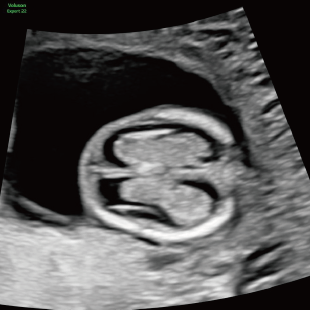

通常の妊婦健診で行う超音波検査では、主に胎児発育(推定体重)、羊水の量、胎児の向きを確認しています。一方で健診の限られた時間内では、胎児を詳細かつ系統的に評価することが難しい場合があります。当院で行っている胎児超音波スクリーニングとは、高性能な超音波検査機器を用いて胎児の発育や形態(からだの構造)をより詳しく観察し、胎児の状態を丁寧に評価する検査です。 出産前に赤ちゃんの状態をより詳しく知りたいという患者さんのご希望にお応えするため、当院では超音波検査士*および超音波専門医・指導医**が胎児超音波スクリーニングを担当します。

Voluson Expert 22®(GEHealthcare)という産婦人科領域におけるハイエンド超音波診断装置を使用しています。 従来機種と比べ、より高精細な画像描出性能と高度な解析機能を備えており、 胎児の発育や形態をより詳細に観察することが可能です。

通常、妊娠期間を通じて初期、中期、後期の3回に分けて行うことをお勧めしています。

妊娠週数により発育段階が異なり、観察しやすい部位や評価できる内容も変化するため、段階的に行うことが重要です。